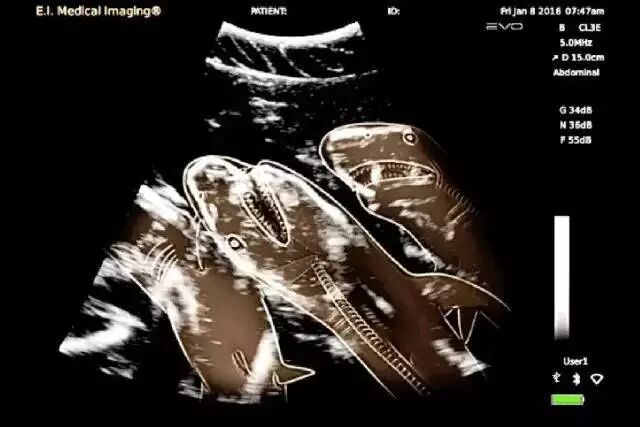

NO.4

<怀孕的鲨鱼>

自然界的杀手!

在肚子里的时候,

竟然有种莫名的喜感……